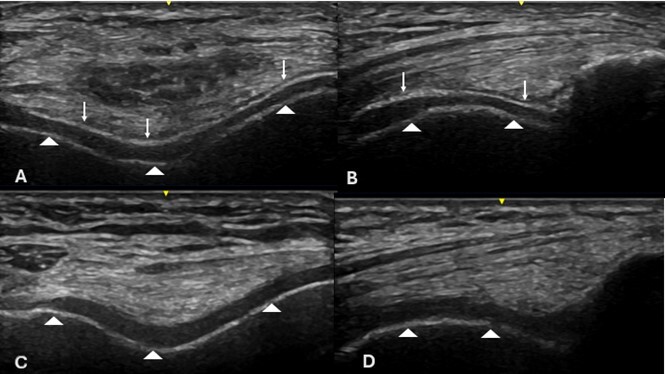

Ultrasonographic image in Double contour sign, suggestive of monosodium urate crystal deposition in hyaline cartilage.

Context: Microcrystalline arthropathies are diseases caused by deposition of crystals within joint and periarticular tissues. Three types of crystals involved in these diseases are monosodium urate, calcium pyrophosphate crystals, and basic calcium phosphate crystals (1). In the case of gout, hyaline cartilage is often the site of monosodium urate crystal deposits, revealing the "Double Contour" (DC) sign, which is a hyperechoic band over the chondrosynovial (superficial) margin, which increases the superficial cartilage interface to a thickness similar to that of subchondral bone (2). (Fig. 1).

Figure 1: Right knee with double-contour sign (DC sign=white arrow; subchondral bone=arrowhead) in a longitudinal and transverse view of the hyaline cartilage (C and D) in a healthy knee, showing only hyaline cartilage and subchondral bone (arrowhead).